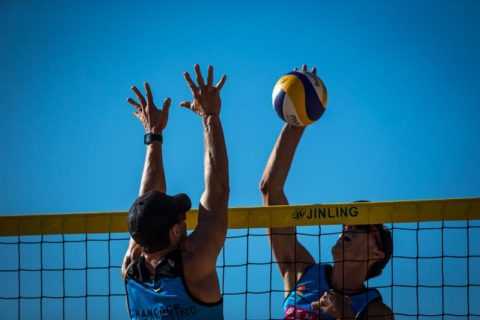

Спортивные нагрузки

Сахарный диабет это образ жизни или болезнь?

Если человек будет слушать своего лечащего врача, он сможет научиться воспринимать заболевание правильно. Во многом этому способствуют корректно подобранные спортивные тренировки.

Обратите внимание! Медики называют спорт «невидимым инсулином». На фоне физической активности снижается потребность в этом элементе.

Таблица 8. Каким спортом можно заниматься диабетикам?

Волейбол Волейбол |

40-80 минут. |